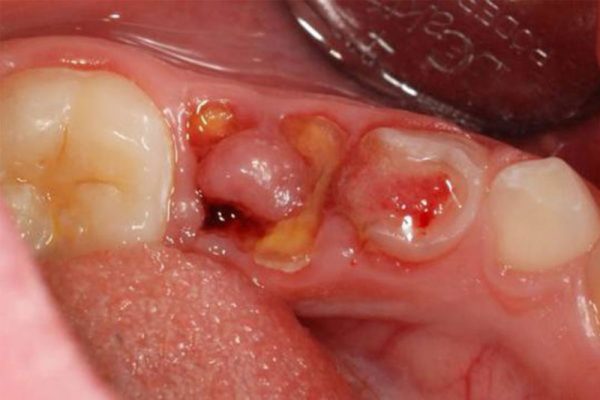

Khi lỗ sâu to dần, những mảnh vỡ trên mặt răng ngày một lớn dần đi kèm với những cơn đau từ răng. Sâu càng nặng, răng tổn thương nghiêm trọng sẽ khiến những mảnh vỡ mẻ càng nhiều hơn. Sâu răng sẽ tấn công hết lớp men và ngà răng ở phần thân răng, khi đó chân răng sẽ lộ ra ngoài.

Những biến chứng khi răng hàm sâu bị vỡ chỉ còn chân răng

- Răng sâu bị vỡ chỉ còn chân răng sẽ gây nhiều biến chứng nặng nề ảnh hưởng đến cuộc sống sinh hoạt hằng ngày. Sâu răng khi không được điều trị kịp thời sẽ hỏng làm men răng, chân răng thậm chí là tủy răng. Khi đó răng không còn khả năng thực hiện chức năng chính là ăn nhai.

- Sâu răng bị vỡ chỉ còn chân răng tạo ra những lỗ hỏng lớn khiến thức ăn dễ rơi vào đó tạo nên chứng hôi miệng khó khắc phục.

- Phần lợi này dễ sưng, dễ chảy máu do bị chà sát khi ăn nhai, dễ viêm nhiễm.

- Có nguy cơ tạo thành áp xe răng.

- Ổ nhiễm trùng từ răng sâu bị vỡ chỉ còn chân răng có thể lan rộng gây viêm xương hàm, lan ra phần mềm và các tổ chức lân cận tạo một ổ nhiễm trùng khó kiểm soát.